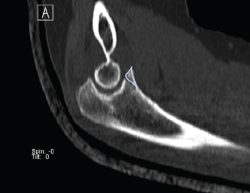

Presentamos el caso de una mujer de 46 años, diestra, sin patología crónica y que trabaja como auxiliar en una residencia geriátrica. Durante su jornada laboral sufre una caída casual presentando dolor y limitación funcional en su codo izquierdo. No presenta deformidades externas en el codo, ni lesiones vasculonerviosas. En el estudio radiológico, se sospecha una fractura de la punta de la apófisis coronoides del codo izquierdo, que correspondería, según la clasificación de Regan y Morrey, al tipo 1 (Figuras 1 y 2). Se comprueba que el codo es estable y se coloca una férula braquial, a la espera de realizar una tomografía computarizada (TC), que confirma la lesión. En la TC podemos visualizar mejor la morfología de la fractura de coronoides tanto en los cortes sagitales (Figura 3), como en los axiales (Figura 4).

Figura 3. Corte sagital de tomografía computarizada, realizado a los 10 días de la lesión. Vemos enmarcada la línea de fractura al nivel de la punta de la apófisis coronoides.

Figura 4. Cortes axiales de tomografía computarizada a los 10 días de la lesión. A: fractura de la punta de la coronoides que se extiende hacia la base de la coronoides; B: fractura conminuta al nivel de la faceta anteromedial de la coronoides.